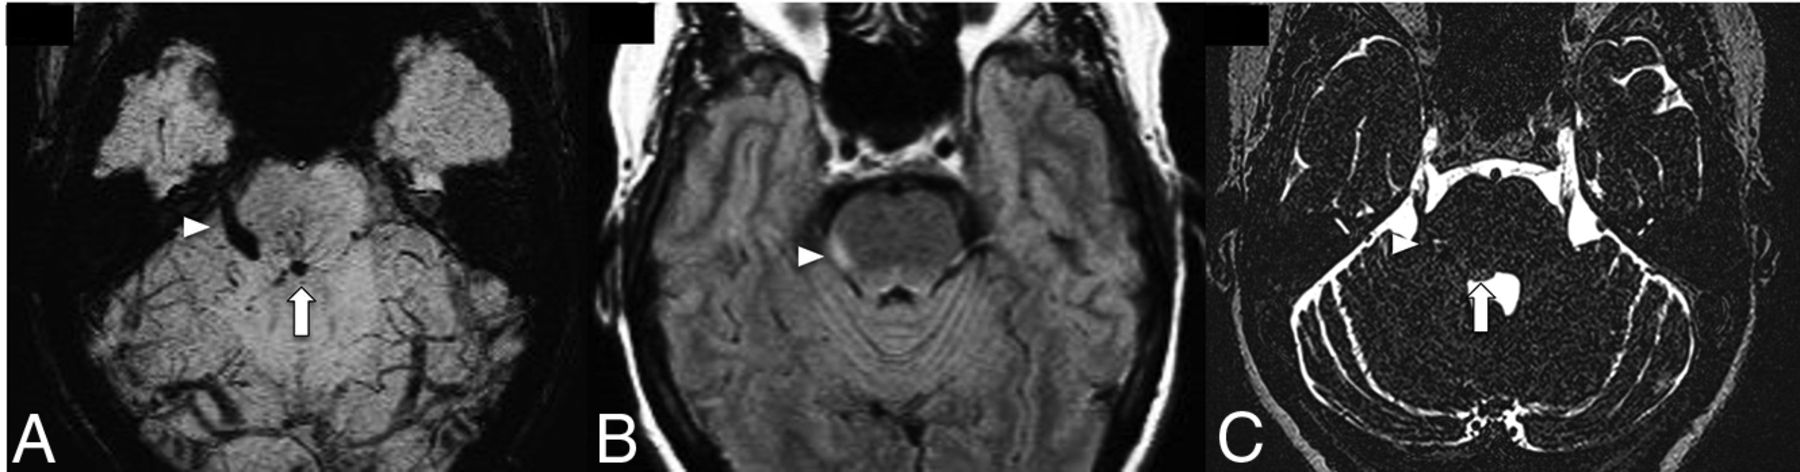

The triggered angiogenesis, which forms fragile vessels prone to hemorrhage as well as recurrent cycles of angiogenesis and microbleeds ultimately lead to the formation of CCMs.10 The following anatomic factors predispose to the development of CCMs within the drainage territory of a DVA: infratentorial DVA location, drainage of the collector into a deep vein, torsion of the draining vein, ≥5 medullary veins draining into a collector, stenosis of >55% of the medullary veins, and an acute angle between the medullary and the collector vein of ≤106.5°.8,11⇓-13 Note that most of the above-mentioned anatomic factors contribute to a decreased outflow of the DVA, thus supporting a venous congestion model of the formation of CCMs in the vicinity of a DVA. Systematic factors such as major infectious illness, chronic inflammatory disorders, and radiation exposure/treatment are also implicated in the formation of CCMs.12 The proinflammatory state is believed to promote thrombosis within the DVA, raising the venous pressure to promote an environment for CCM formation.12 Topographical location of CCMs are important as cortical or juxtacortical location or limbic involvement are more prone to seizure.14 Brainstem CCM may cause cranial neuropathy through the involvement of the cranial nerve nuclei, intra-axial cranial nerve pathway or even direct extension into the cisternal cranial nerves (Fig 2).15 Hemorrhagic propensity of CCM hemorrhage is based on the history of prior hemorrhage and this can be quantitatively analyzed through the CCM hemosiderin burden and its evolution over time on quantitative susceptibility mapping (QSM).16,17 Higher mean susceptibility value on QSM positively correlates with patient age and prior hemorrhagic episodes, whilst patients with clinically stable CCM demonstrate lower mean susceptibility value (Fig 3).16,17

A patient with right facial pain and dysesthesia. SWI (A) shows a posterior pontine DVA (arrow) and an associated CCM (arrowhead) involving the intra-axial and cisternal segments of the right trigeminal nerve. FLAIR (B) demonstrates hyperintense edema along the right lateral aspect of the pons (arrowhead). Coregistered T2 sampling perfection with application-optimized contrasts by using different flip angle evolutions (SPACE sequence; Siemens) (C) confirms CCM involvement of the right trigeminal nerve.

A middle-aged patient with new-onset ataxia. T1WI (A) and SWI MIP (B) show a CCM in the right superior cerebellar peduncle (arrowheads) and a large left cerebellar DVA with the collector vein (arrow) draining into the transverse sinus. Quantitative susceptibility mapping (C) analysis of the CCM shows a high mean susceptibility value of 858 parts per billion (with threshold). An ROI with a red boundary represents the exclusive object boundary, and the purple area represents thresholded pixels (150 parts per billion). SWIM (Siemens) parameters: TE = 20.00 ms; TR = 27.00 ms; flip angle = 150; resolution = 0.937 × 0.937 ×2.5 mm. Images courtesy of Dr E. Mark Haacke.